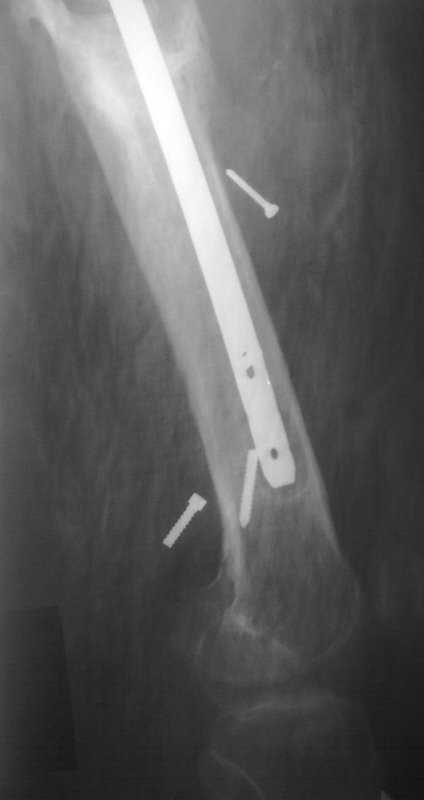

Уважаемый Илья! Если я правильно понял, фистулография у Вас - вторая картинка, а ранки на первой фотографии в области нижних блокирующих винтов и приблизительно на уровне псевдоартроза. Хотелось бы уточнить, есть ли клинические проявления свища на уровне псевдоартроза, отделяемое и т. д. Это существенно влияет на план операции - если перелом неинфицирован,а инфекция только на уровне нижних блокирующих винтов, достаточно удалить конструкции, те, что доступны, не стоит гоняться за кончиками винтов, произвести остеосинтез по Илизарову (на уровне малого вертела стержни, конечно)с п о с т е п е нн о й коррекцией угловой и ротационной деформаций. Параллельно ревизовать место расположения нижнего блокирующего винта, рассверлить, почистить, дренировать.